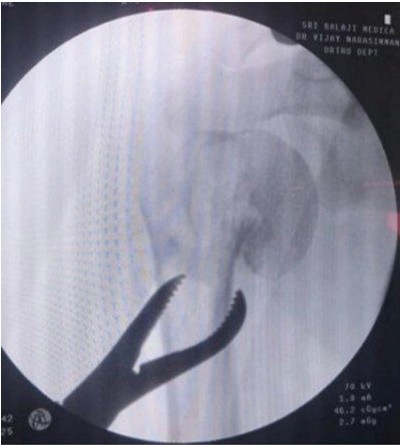

Informed consent was obtained from all participants. Demographic details and relevant medical history were collected using a structured proforma. Clinical examination and surgical intervention were carried out using standard procedures at the SBMCH. [Fig. 1] [Fig. 2] [Fig. 3] Postoperative evaluation for implant loosening was done through serial radiographs, specifically assessing for radiolucency at the bone-cement interface. Functional outcomes were assessed 26 using the CONSTANT-Murley score and UCLA shoulder score. All data were entered in Microsoft Word and analyzed using SPSS software version 24. [Fig. 4].

Figure 2: C-ARM image.